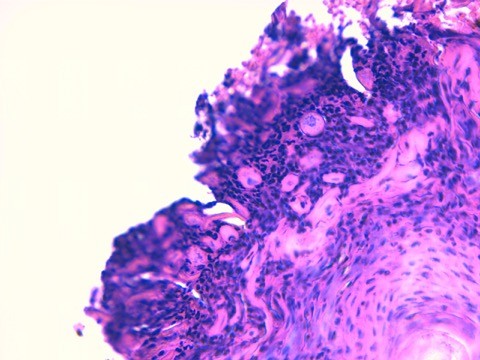

@ Biopsies (LAPVSO) : « Quatre biopsies cutanées sont examinées selon différents niveaux de section et après réaction au PAS.

L’épiderme apparaît multifocalement creusé de vésiculo-pustules relativement étendues. Elles peuvent se développer sous la couche cornée ou dans la couche granuleuse ou ponter plusieurs abouchements folliculaires contigus. Les squamo-croûtes ou les vésiculo-pustules contiennent des cellules épithéliales acidophiles, acantholysées, mêlées à des granulocytes neutrophiles ou éosinophiles et à des lamelles de kératine. Sur le plancher des vésiculo-pustules, constitué de l’épiderme et des infundibula folliculaires, on observe nettement un détachement, par plages, d’acanthocytes qui s’arrondissent, deviennent acidophiles, bombés, présentant encore un noyau viable. Le siège de ces pustules acantholytiques réside le plus souvent dans la couche granuleuse de l’épiderme ou au dessus dans la couche cornée. Le derme sous-jacent est paradoxalement peu inflammatoire. On y observe un infiltrat périvasculaire à diffus, exsudatif, relativement riche en cellules mastocytaires et en granulocytes éosinophiles, accompagnés de quelques lymphocytes. »

Photo 15 : histologie, présence de cellules acantholytiques dans la croûte

Aspect histologique d’une pustulose sous cornée granulocytaire acantholytique amicrobienne sans détection d’éléments figurés pathogènes ni parasitaires ni fongiques.

Aspect histologique orientant vers un pemphigus superficiel auto-immun ou éventuellement une éruption médicamenteuse mimant un pemphigus superficiel.